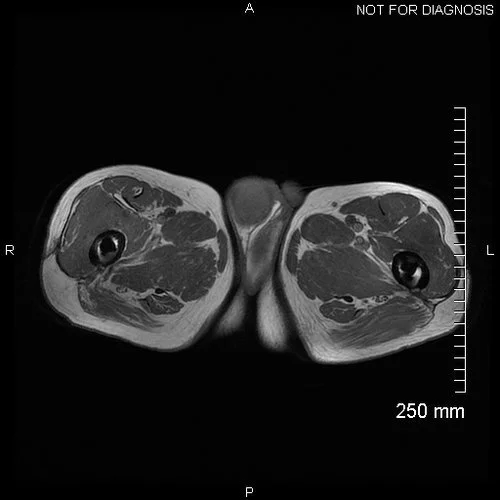

We requested an MRI pelvis to assess soft tissue changes (see below).

Axial MRI showing significant fluid collections around both hips, with considerable abductor muscle destruction. The fluid collection around the right hip extends to the wound.